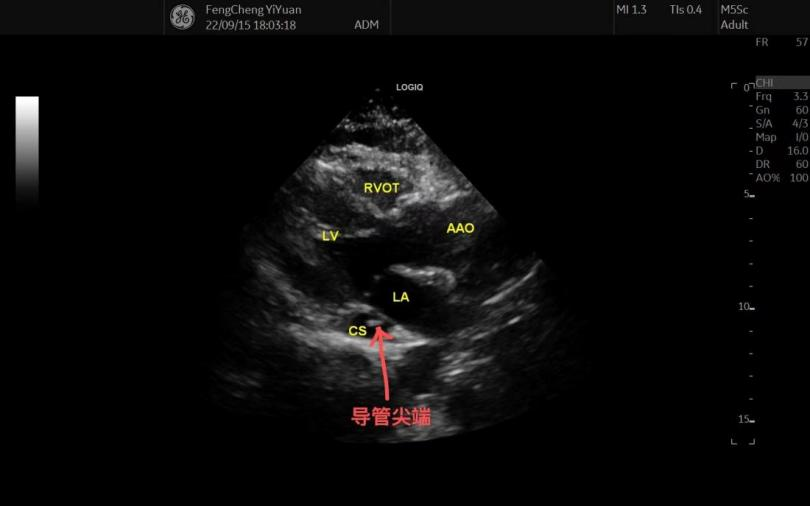

随即我们对患者进行了心脏超声检查,确定该患者为“永存左上腔静脉”。

因超声显示导管尖端位于冠状静脉窦内,位置过深,查阅资料提出,经左上腔静脉置入PICC导管尖端应位于其中下段,若进入冠状静脉窦或右心房则可能会引起心律失常、心绞痛等情况的发生,随即向患者交代所面临的问题,患者表示理解,并选择调整导管尖端位置后保留导管。

随后再次进行了心脏超声,冠状静脉窦内无导管尖端显影,推注生理盐水后右心房内可见少量液体流动,胸片定位最终确定导管尖端位于第七胸椎左侧水平,该导管可安全使用。